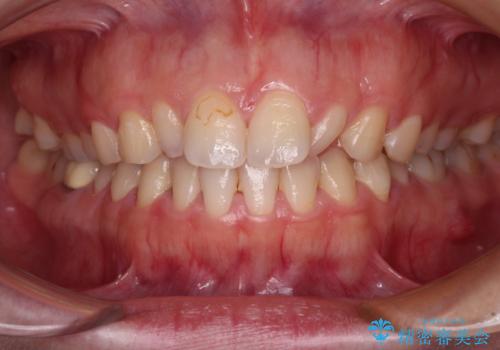

- 前歯の矮小歯と捻れや変色を気にして来院された患者様です。

結婚式が近いということもあり、前歯4本をオールセラミッククラウンにて補綴治療することとしました。